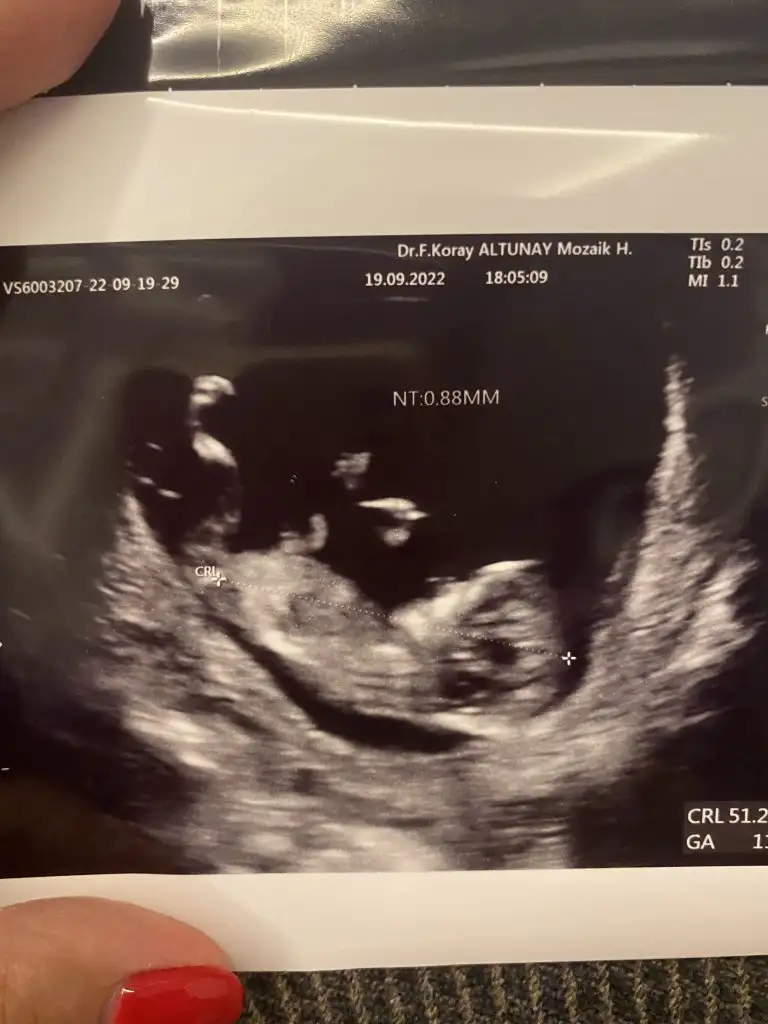

Merhaba ben mayıs annesiyim ama ramzi teorisi çok konuşulmuş. 5+2 bugünkü görüntümü yorumlar mısınız ramziye göre 😊 karından ultrason

• DD7044B8-DDF8-471B-BC8B-DA23E25DA063.webp

DD7044B8-DDF8-471B-BC8B-DA23E25DA063.webp

22,9 KB · Görüntüleme: 97